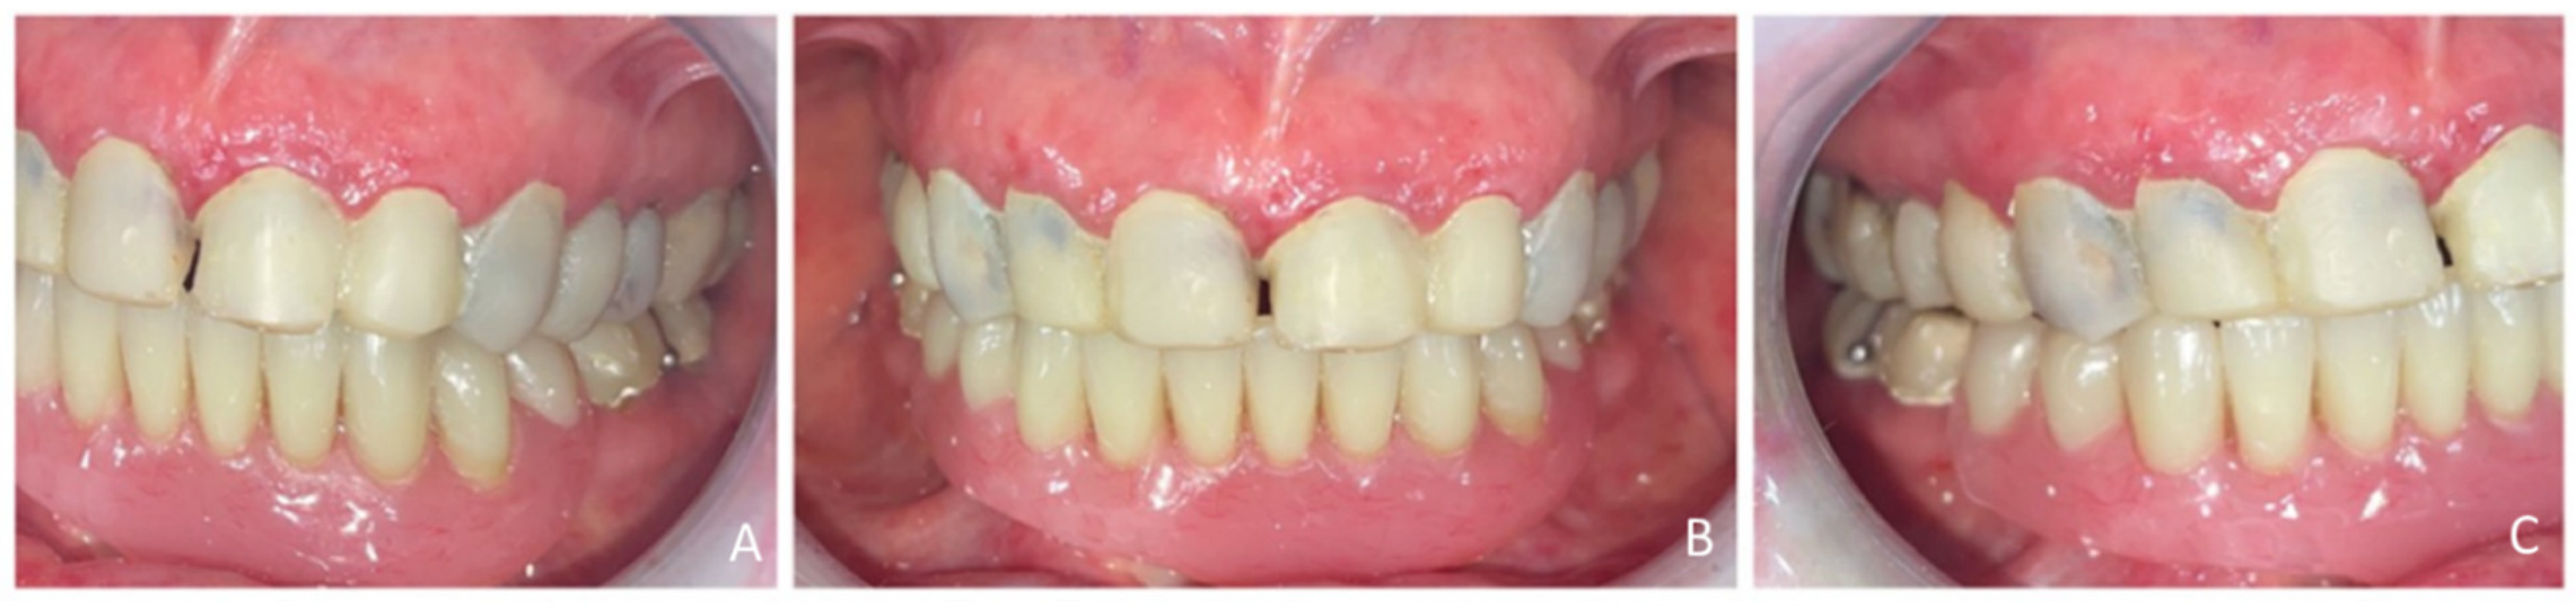

2.4.1. Step 1: Diagnostic Set-Up and Provisional Prosthesis

2.4.3. Step 3: Definitive Prosthetic Rehabilitation